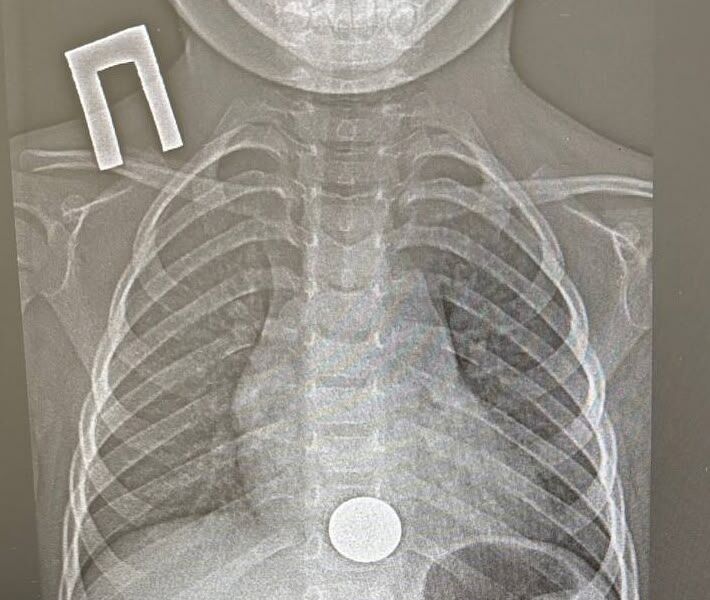

Пациенту провели рентген и обнаружили у него инородное тело в пищеводе, детский врач выполнил эндоскопическое удаление монетки. Вся процедура заняла около минуты.